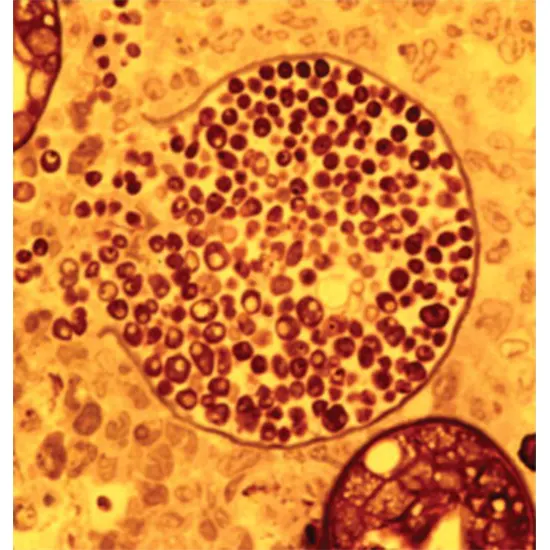

Coccidioides immitis and Coccidioides epistasis is dimorphic fungi, with the potential they can exist in two wonderful types relying on their environment. In their herbal habitat, these fungi exist as filamentous mold, however,r when they are inhaled into the lungs of human beings or animals, they seriously change into a yeast form.

The transformation into the yeast structure is precipitated by using modifications in temperature and different environmental elements in the host's body. The yeast shape of these fungi is accountable for inflicting disease.

Once inner the body, the yeast structure of Coccidioides immitis and Coccidioides posadasii can multiply hastily and set off an inflammatory response. This can lead to the formation of granulomas (small nodules of immune cells) in the lungs, which can purpose signs and symptoms such as cough, chest pain, and shortness of breath.